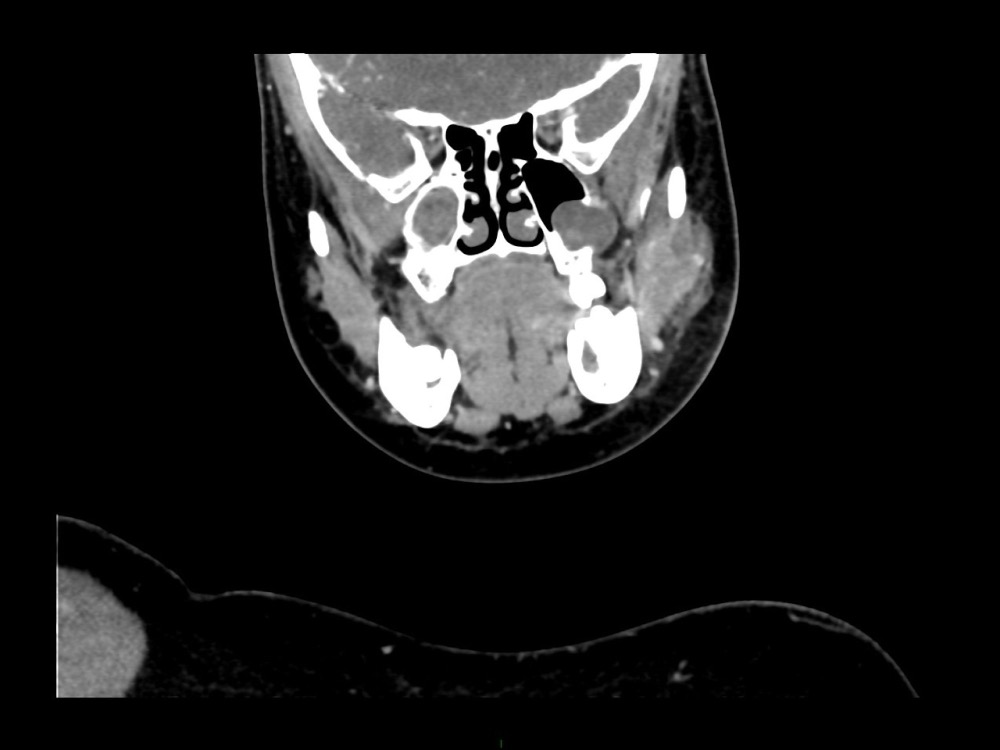

Arsovic / Perrot / Miquel 18/05/2022